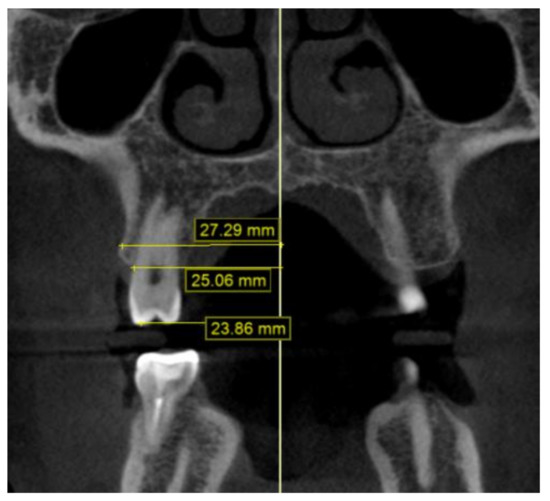

2.2. Methodology of Measurements